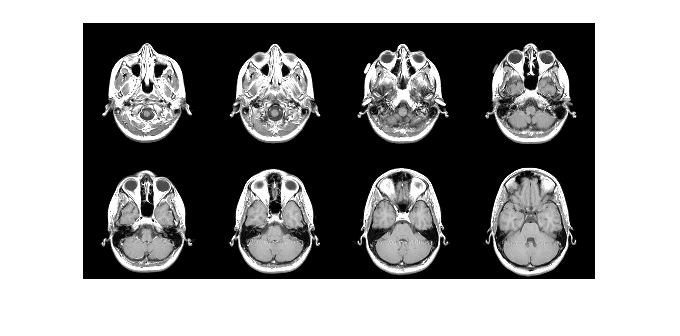

imtile

Combine multiple image frames into one rectangular tiled image

returns a tiled image containing the images in the files with file names

out = imtile(filenames)filenames.

By default, the imtile function arranges the images so that they

roughly form a square. You can change the arrangement using optional name-value arguments.